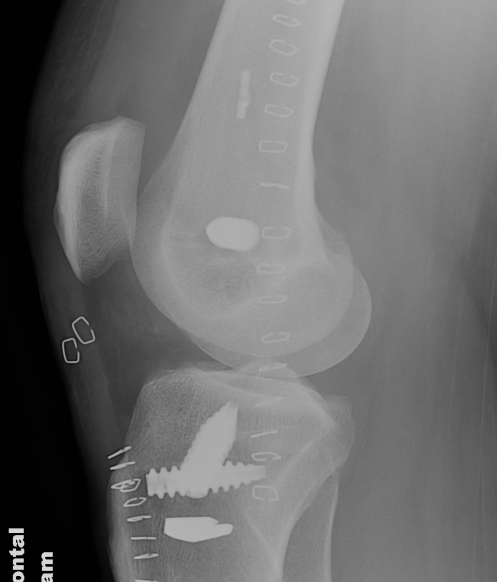

ACL + LaPrade reconstruction of LCL and popliteus